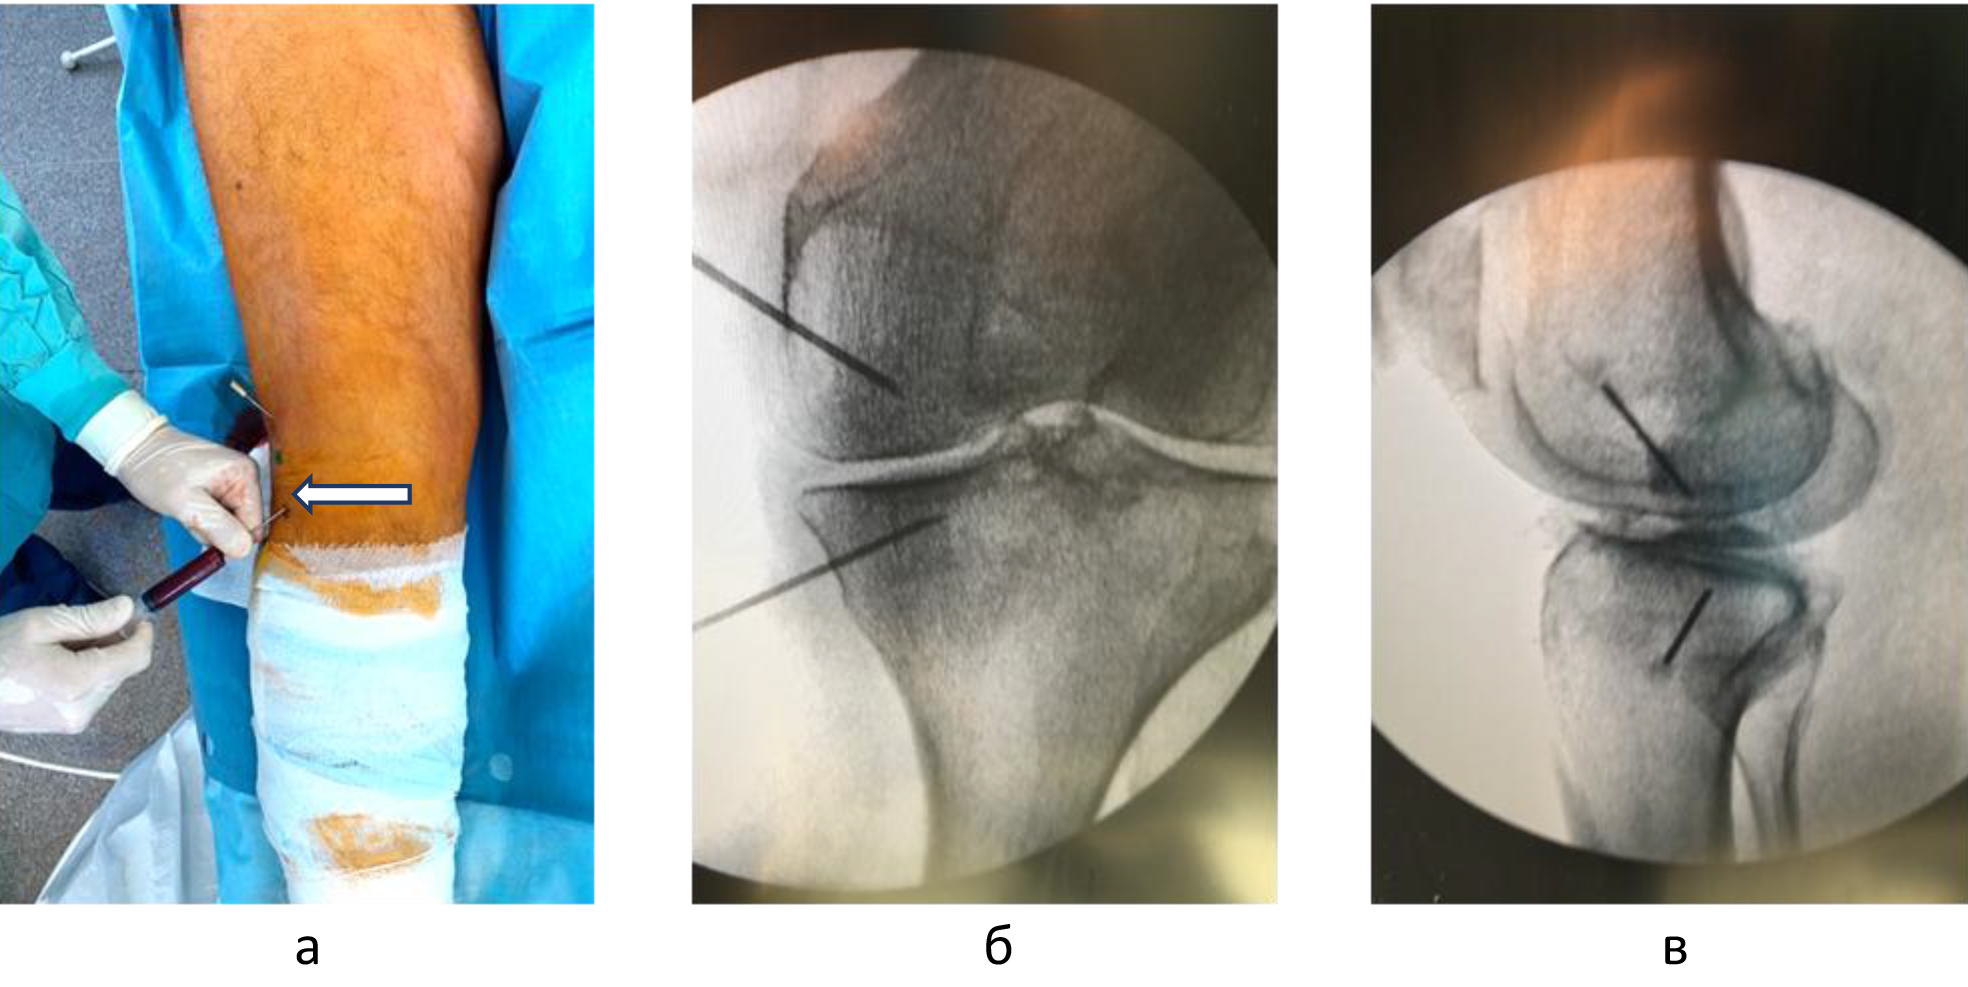

Внутрикостные инъекции ККМ и ОТП выполняли в условиях операционной. Используя 2%-й раствор лидокаина, инфильтрировали мягкие ткани по внутренней или наружной поверхности коленного сустава на 2 см проксимальнее и на 2 см дистальнее уровня суставной щели. Троакары вводили в кость вкручивающими движениями под углом 45 градусов по отношению к оси конечности и продвигали на глубину 1,5 см, достигнув субхондральных структур. Позиционирование троакаров оценивали с помощь электронно-оптического преобразователя (ЭОП) в 2 стандартных проекциях (рис. 3).